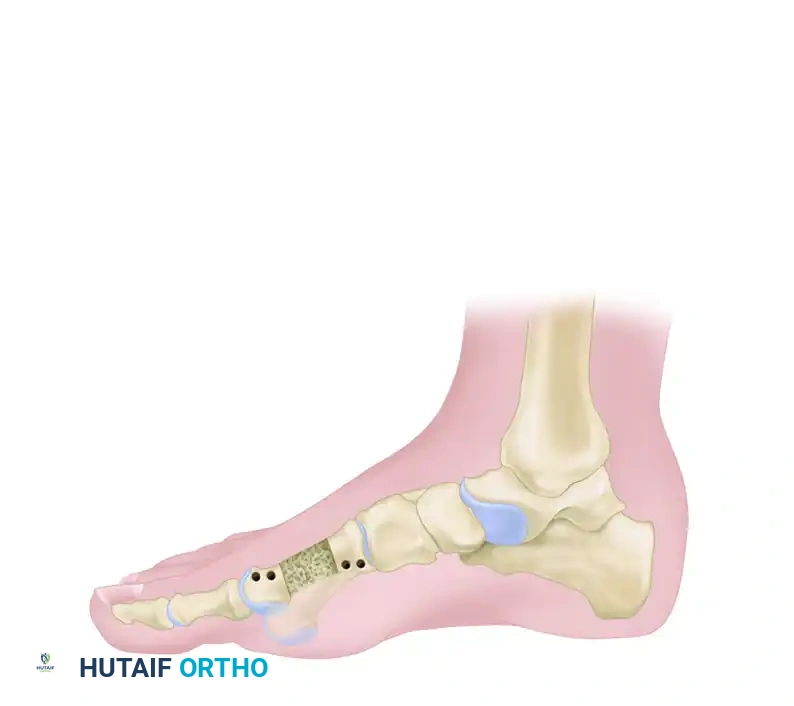

Figure 8: Lengthening of the metatarsal utilizing a one-stage allograft interposition technique. Rigid internal fixation (typically with a plate or intramedullary K-wire) is required to stabilize the intercalary graft.